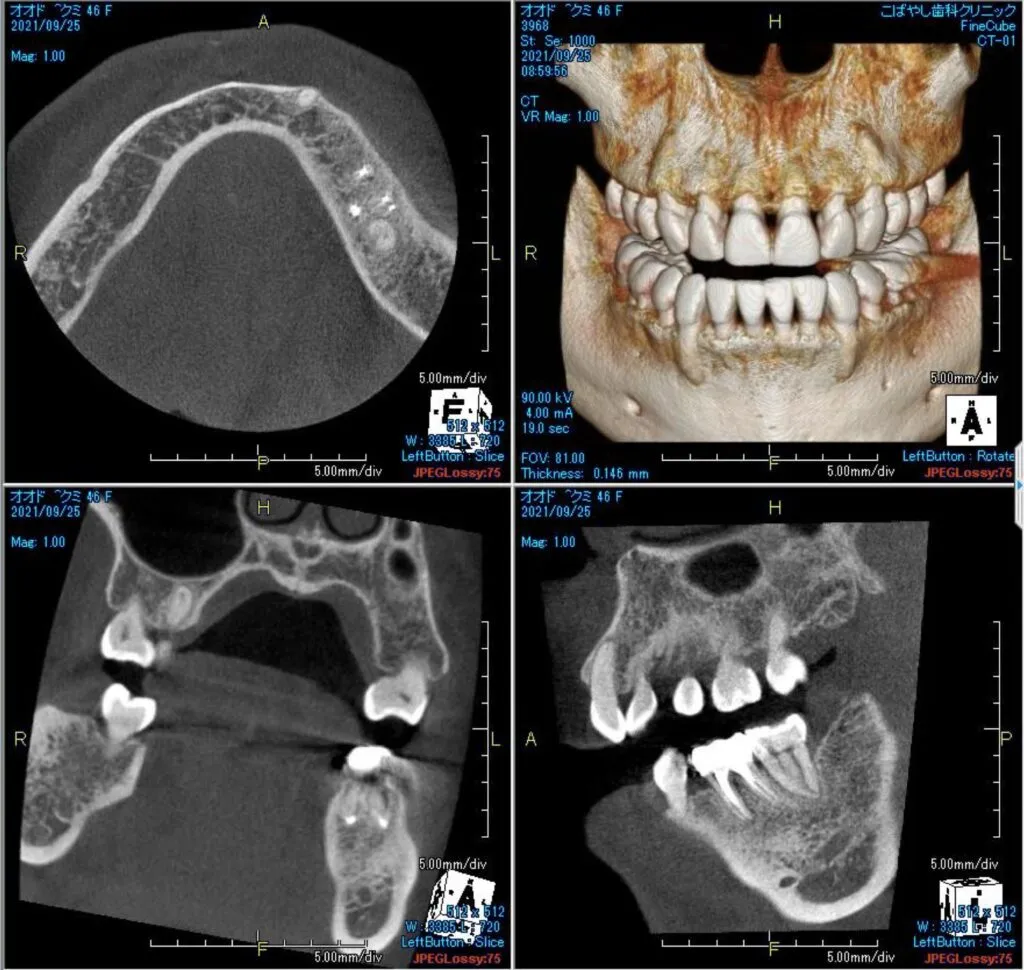

症例

患者様のお悩み | 左下が痛くて噛めない |

|---|---|

治療法・使用素材 | 自費根管治療・補綴処置・オールセラミック |

患者様の年代 | 30代 |

治療開始年齢 | 36歳 |

治療にかかった期間 | 6ヶ月 |

性別 | 女性 |

この治療のリスクについて | 病態が改善しないかもしれない |

治療にかかった費用 | 30万 |

治療前

治療後